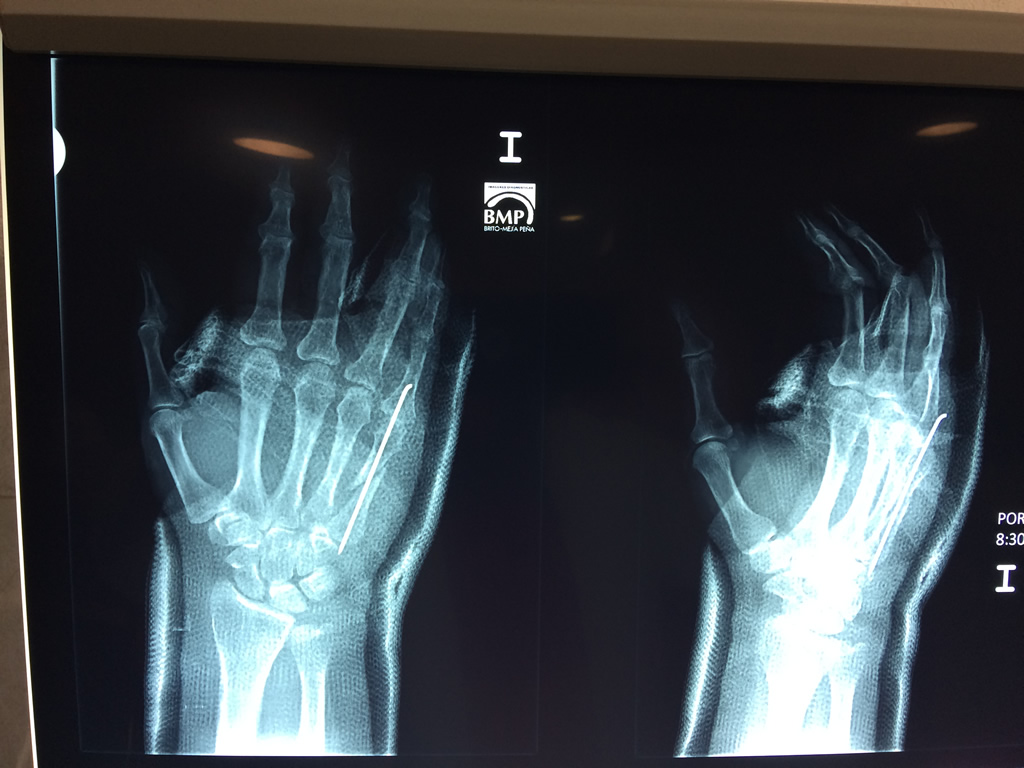

Calcaneo - Cirugías de Muñecas y Manos

Los procedimientos más comunes en cirugía de la mano son aquellos destinados a reparar traumatismos, incluyendo lesiones de tendones, nervios, vasos sanguíneos, y articulaciones; huesos fracturados; y quemaduras, cortes, y otros daños de la piel.